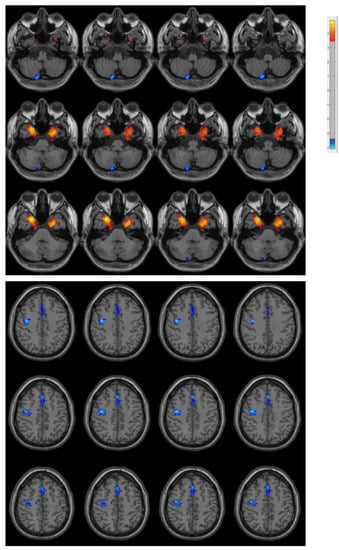

| Region | Cluster Size (Voxel) | MNI (x, y, z) | t-Value |

|---|---|---|---|

| Right Posterior Cerebellar Lobe | 17 | (15, −81, −54) | −5.5695 |

| Left Medial Temporal Lobe | 52 | (−27, 0, −42) | 5.1186 |

| Right Medial Temporal Lobe | 74 | (27, 9, −39) | 5.4905 |

| Right Precentral Gyrus | 123 | (39, −9, 42) | −5.7469 |

| Supplementary Motor Area | 70 | (0, 24, 48) | −5.2007 |

3.2. Difference in ReHo between PD Patients and Controls